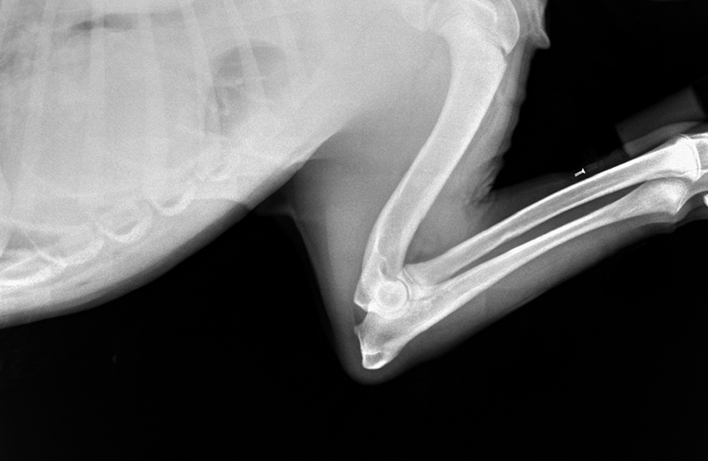

RTG Dysplazie loketního kloubu (DLK)